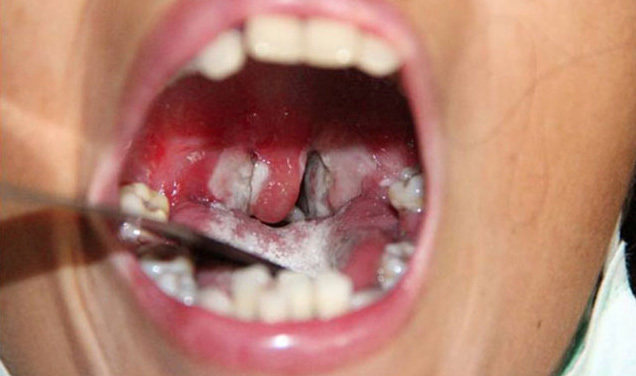

- Bạch hầu thể họng: sốt nhẹ, đau họng, ho, khàn tiếng, chán ăn. Sau 2-3 ngày, xuất hiện giả mạc hai bên thành họng, có màu trắng ngà, xám, đen, dai, dính, dễ chảy máu. Bệnh có thể qua khỏi hoặc trở nên trầm trọng và tử vong trong vòng 6-10 ngày.

- Trường hợp bệnh nặng không có biểu hiện sốt cao nhưng có thể sưng cổ và làm hẹp đường thở.